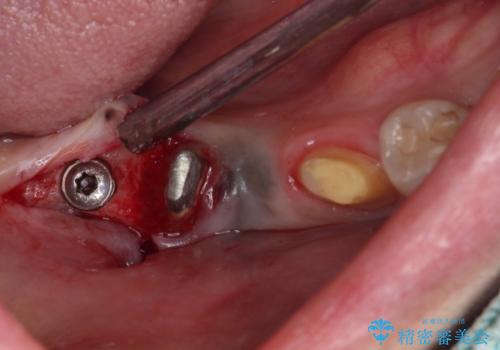

治療を終えたばかりですが、出血を改善するためには作り直しが必要と判断し、オールセラミッククラウンにて補綴治療することとしました。

他にも、咬合時に痛みを感じる歯や、欠損により咬みにくい奥歯などをインプラントを用いて治療を行うこととしました。

右下は、残存歯の状態があまり良くなかったため、今後抜歯となったことを想定して、最後臼歯のインプラントを決定しました。

- 外科手術のため、術後に痛みや腫れ、違和感を伴います